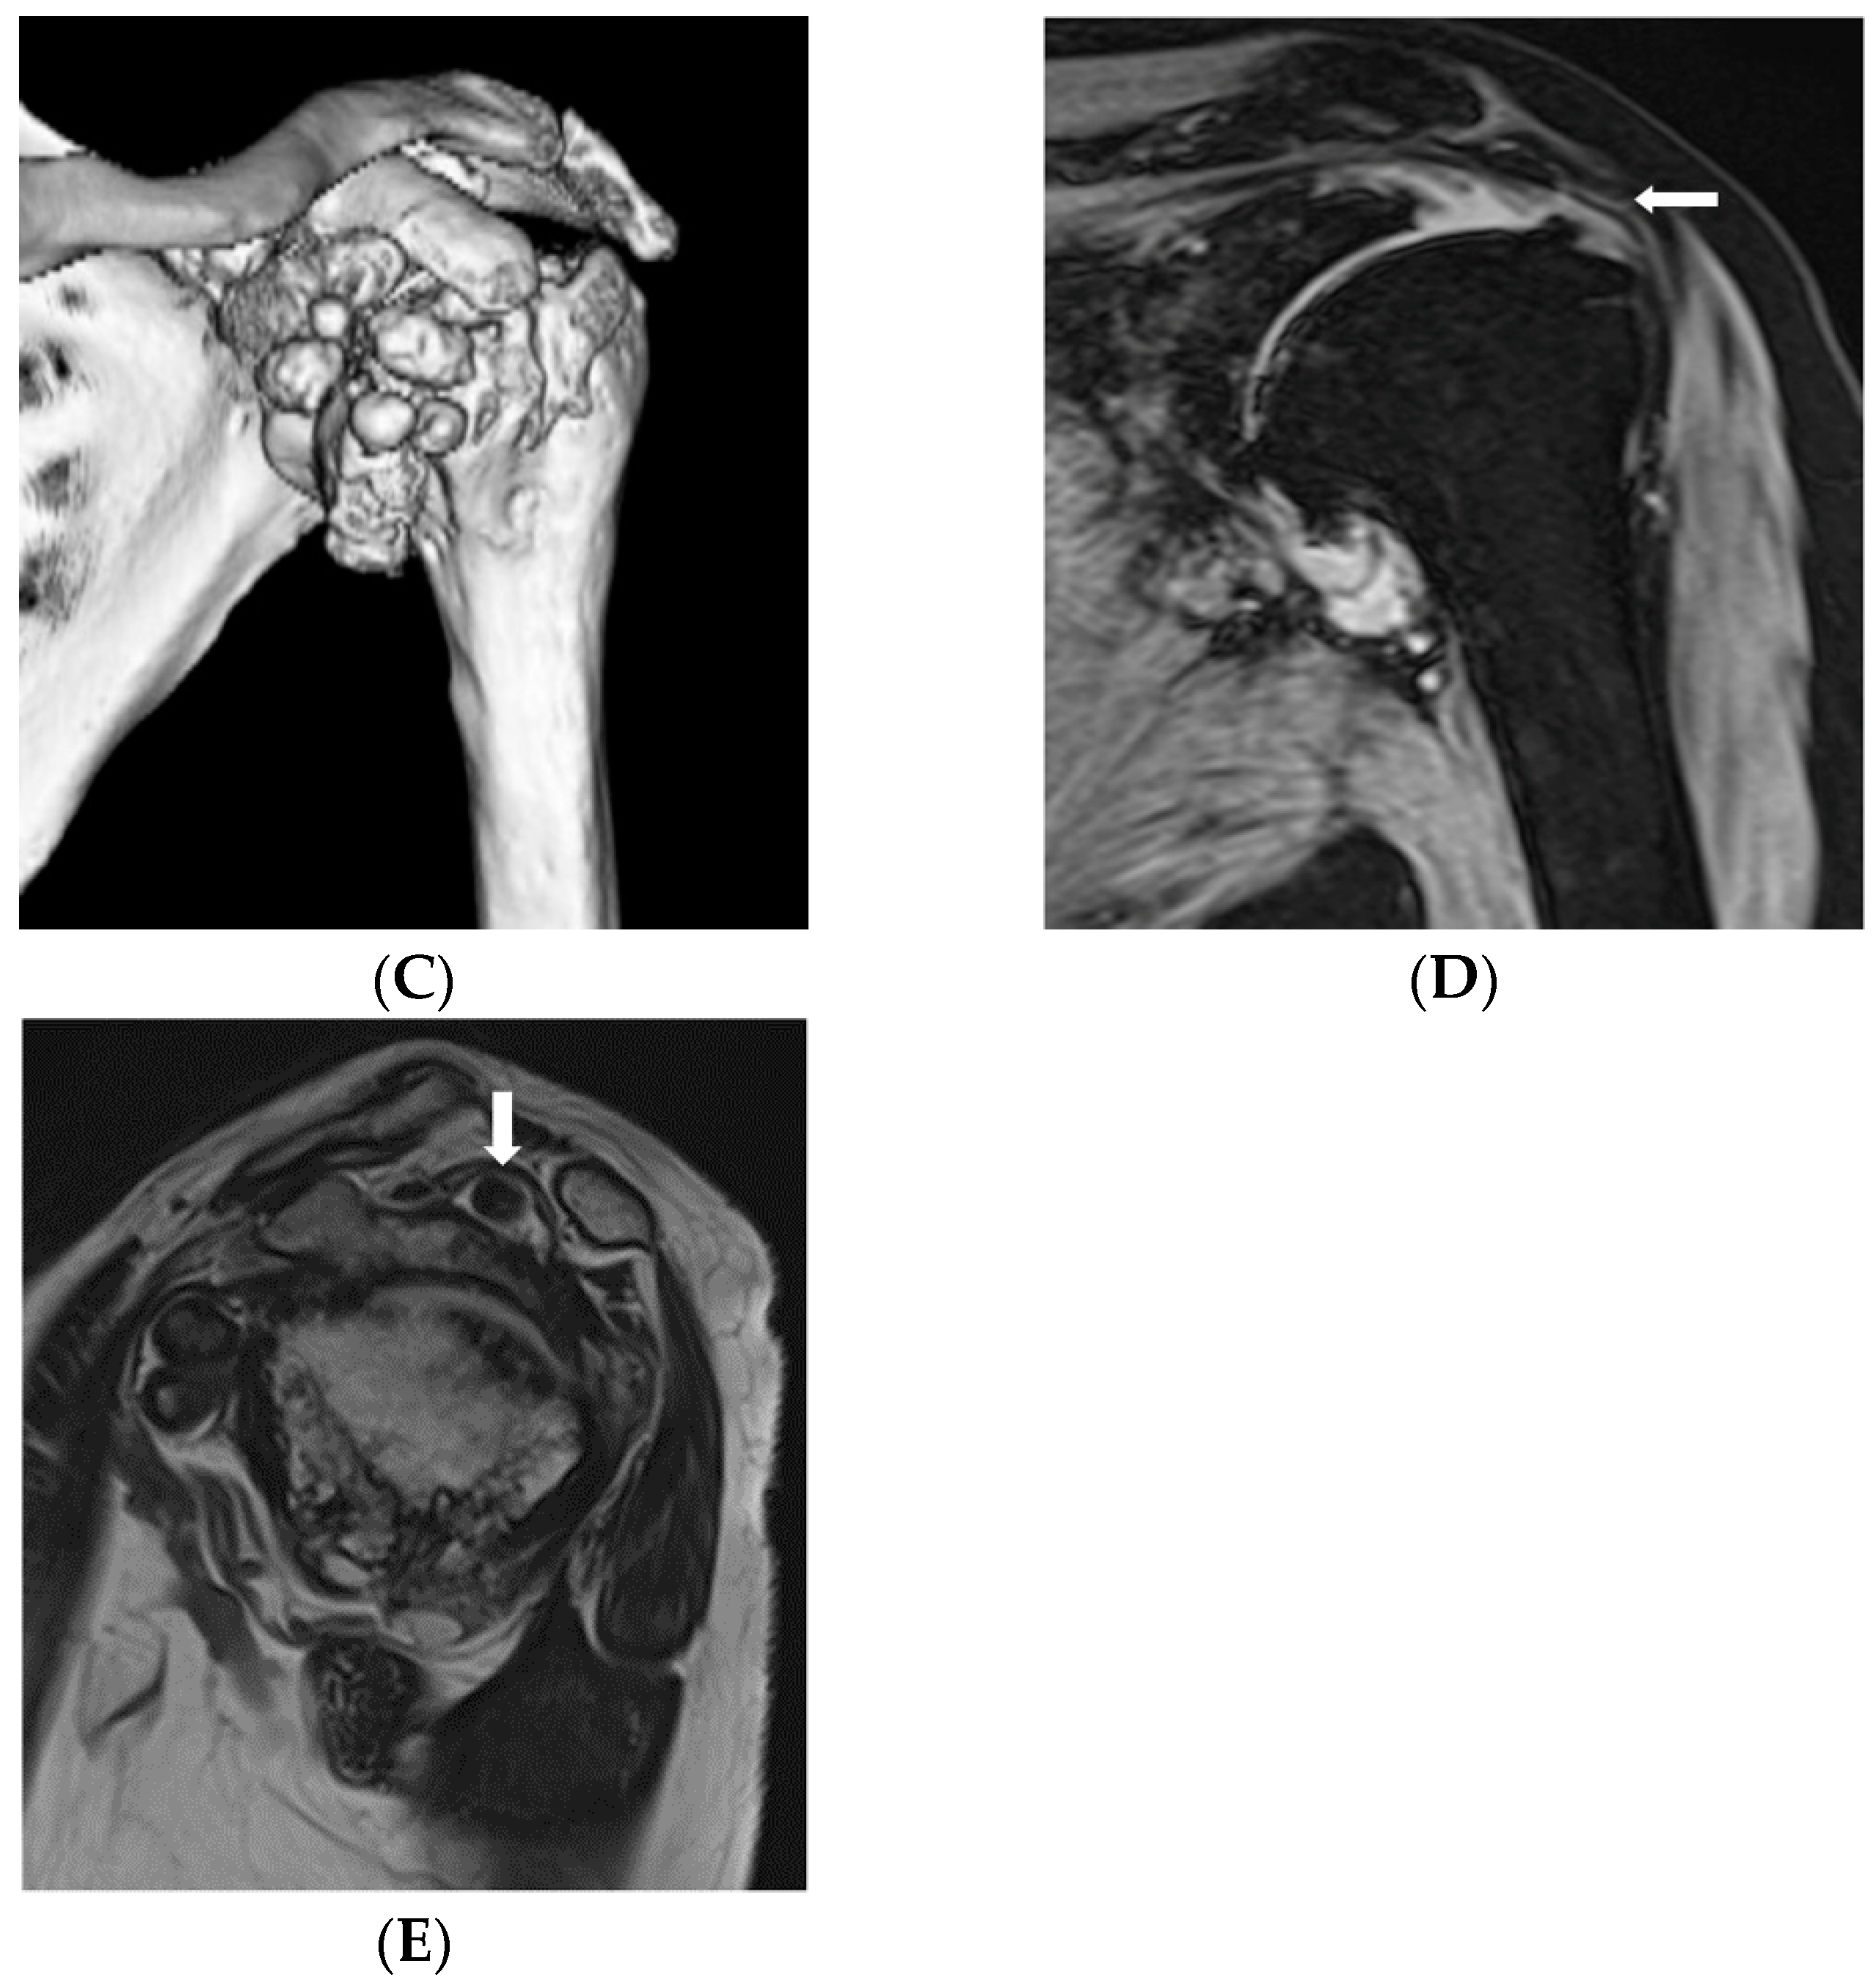

Reverse Shoulder Arthroplasty for Primary Synovial Osteochondromatosis of the Shoulder with Massive Rotator Cuff Tear and Marked Degenerative Arthropathy

2. Case Report

2.1. Case Introduction